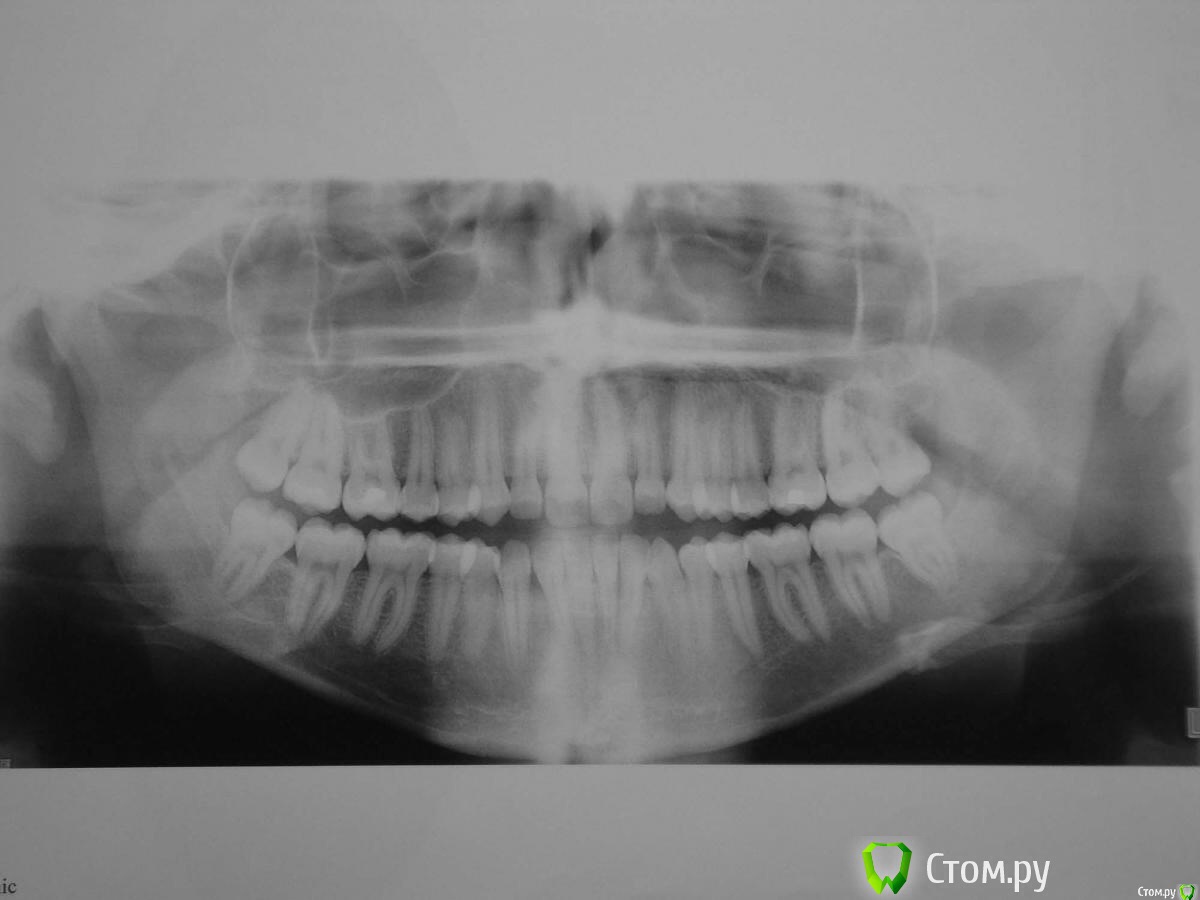

lana77777 Опубликовано 16 мая, 2015 Поделиться Опубликовано 16 мая, 2015 Здравствуйте уважаемые врачи!Очень нужен ваш совет!Пожалуста не проходите мимо!.Очень много вопросов ,помогите разобраться:девушка 20 летПредстоит удаление сначала нижних, потом отдельно верхних зубов мудрости .Как удаление зубов мудрости повлияет на внешний вид?Посмотрите пожалуйста снимок ,насколько это будет сложно,насколько близко к нерву располагаются нижние зубы мудрости? Врач предлагает удалять под седацией насколько опасен этот вид наркоза,как избежать осложнений ?Какие вопросы следует задать врачу перед удалением и на что обратить внимание?Можно ли матери присутствовать при удалении зубов? Как к этому относиться врачи не раздражает ли их это? Как мама очень переживаю.....Пожалуста выскажите свое мнение в этой ситуации. Нужно принять правильное решение. Заранее спасибо за ответы Ссылка на комментарий

red_butler Опубликовано 16 мая, 2015 Поделиться Опубликовано 16 мая, 2015 Как удаление зубов мудрости повлияет на внешний вид?никак не скажется Посмотрите пожалуйста снимок ,насколько это будет сложно,насколько близко к нерву располагаются нижние зубы мудрости? зубы не сложные Врач предлагает удалять под седацией насколько опасен этот вид наркоза,как избежать осложнений ?Седация не наркоз. http://forum.stom.ru/topic/1964-pokrikivaniia-dushi/Избежать осложнений - задача анестезиолога. Можно ли матери присутствовать при удалении зубов?На усмотрение врача, но зачем? 1 Ссылка на комментарий